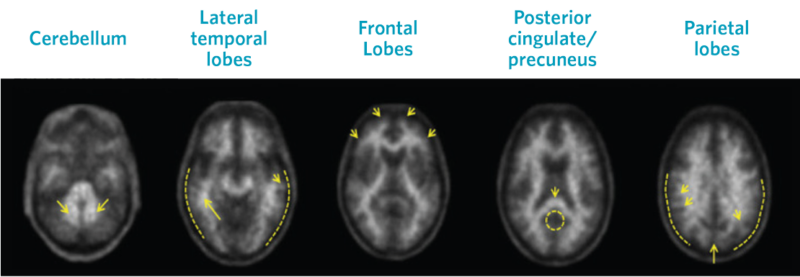

Neuraceq® is an accurate diagnostic tool to aid in the evaluation of cognitive decline.1 Neuraceq® reveals β-amyloid neuritic plaques in different brain regions, thereby allowing an estimate of plaque density by degree of uptake.1

Visual assessment is based on the systematic comparison of tracer uptake in gray and white matter, focusing on specific cortical regions, as seen in greyscale images.

Positive Scans

Images show positive scans with equal or higher tracer uptake in gray matter than white matter and moderate to frequent β-amyloid neuritic plaques